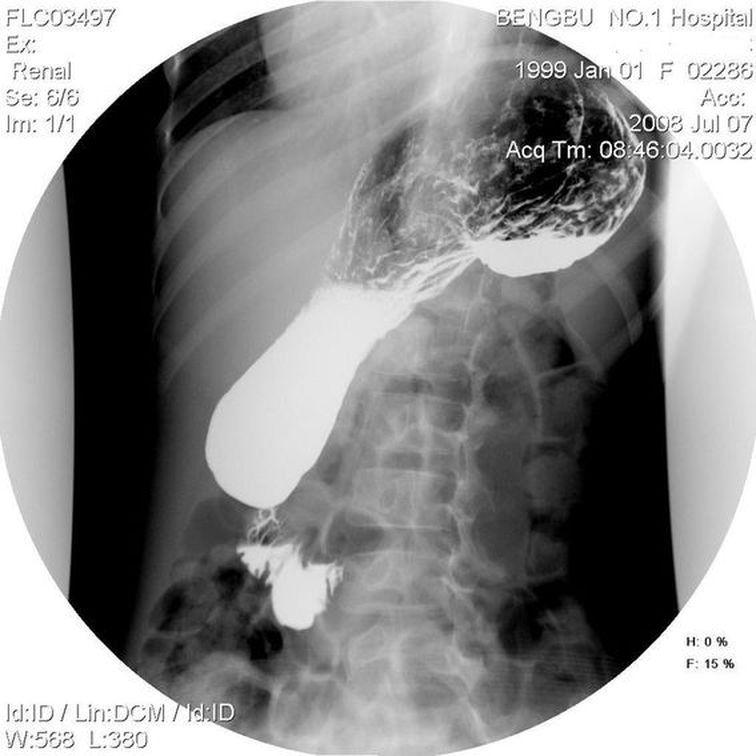

标题: PED1730:女,10岁,以上腹不适就诊。

考虑-----绕胃纵轴旋转型胃扭转可能性 大

但不 能除外---瀑布型胃---请给正位片鉴别

瀑布型胃?器官轴型胃扭转?

考虑1胃扭转?2十二指肠淤滞症(笔杆状压迹)?

可见双液平面,支持考虑胃扭转

支持考虑胃扭转